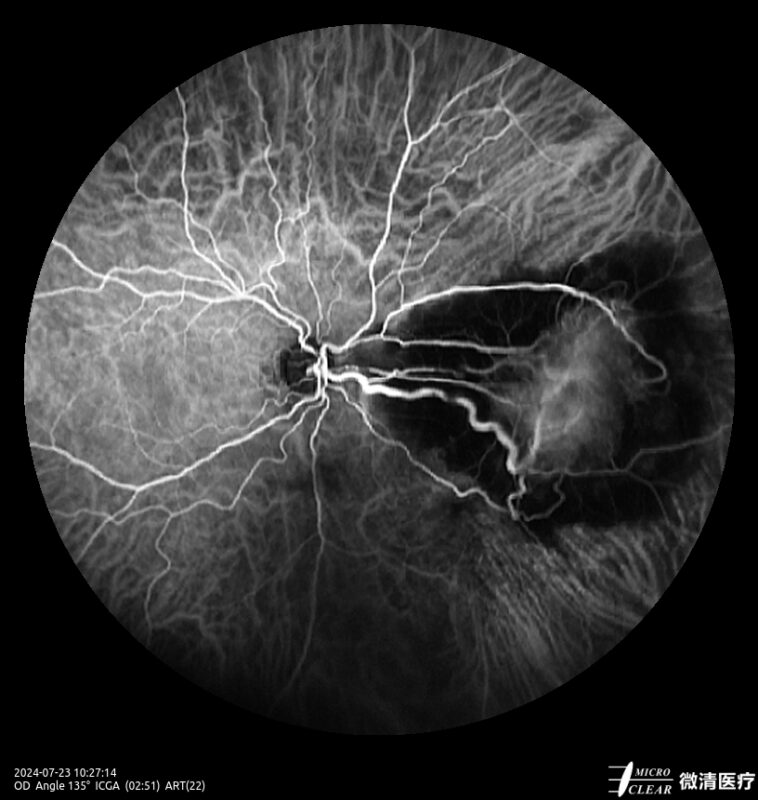

Ultra-groothoek en multimodale fundusangiografie gebaseerd op confocale scanning laser oftalmoscopie (CSLO).

- Fundusfluoresceïne-angiografie (FFA)

- 135° WA (Groothoekangiografie) – in één opname

Confocale Scanning Laser Oftalmoscoop (CSLO)

- Combinatie van drie confocale laserbronnen voor maximaal contrast en getrouwheid.

- Verbeterd confocaal ontwerp zorgt voor een betere scheiding van de netvlieslagen en verbeterde penetratie door cataract en oculaire troebelingen.